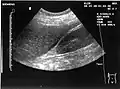

Ultrasound of liver (left side of the image) and right kidney (right side of the image) and Morison's pouch, not containing fluid- Abdominal CT, showing Morison's pouch as the dark margin surrounding the right kidney (at lower left corner of image)